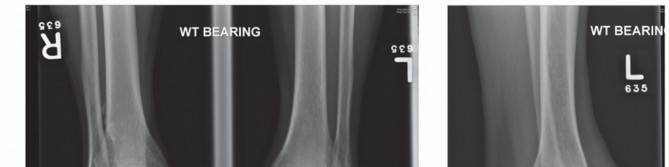

DEFINITION End-stage ankle arthritis failing to respond to nonoperative treatment ANATOMY Ankle Tibial plafon…